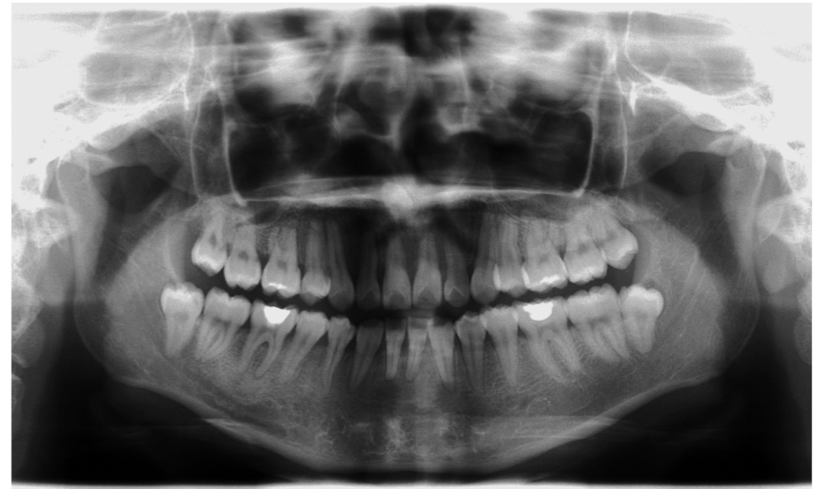

图1 全景片全景片显示下颌骨的组成